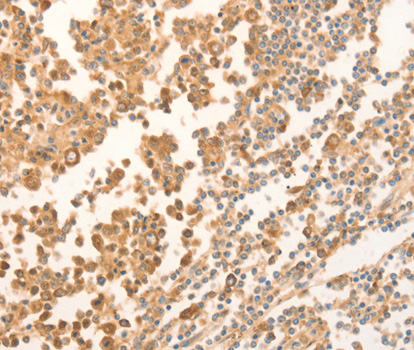

• A2769: image 2

Immunohistochemistry of paraffin-embedded human tonsil tissue using NAP1L1 antibody.